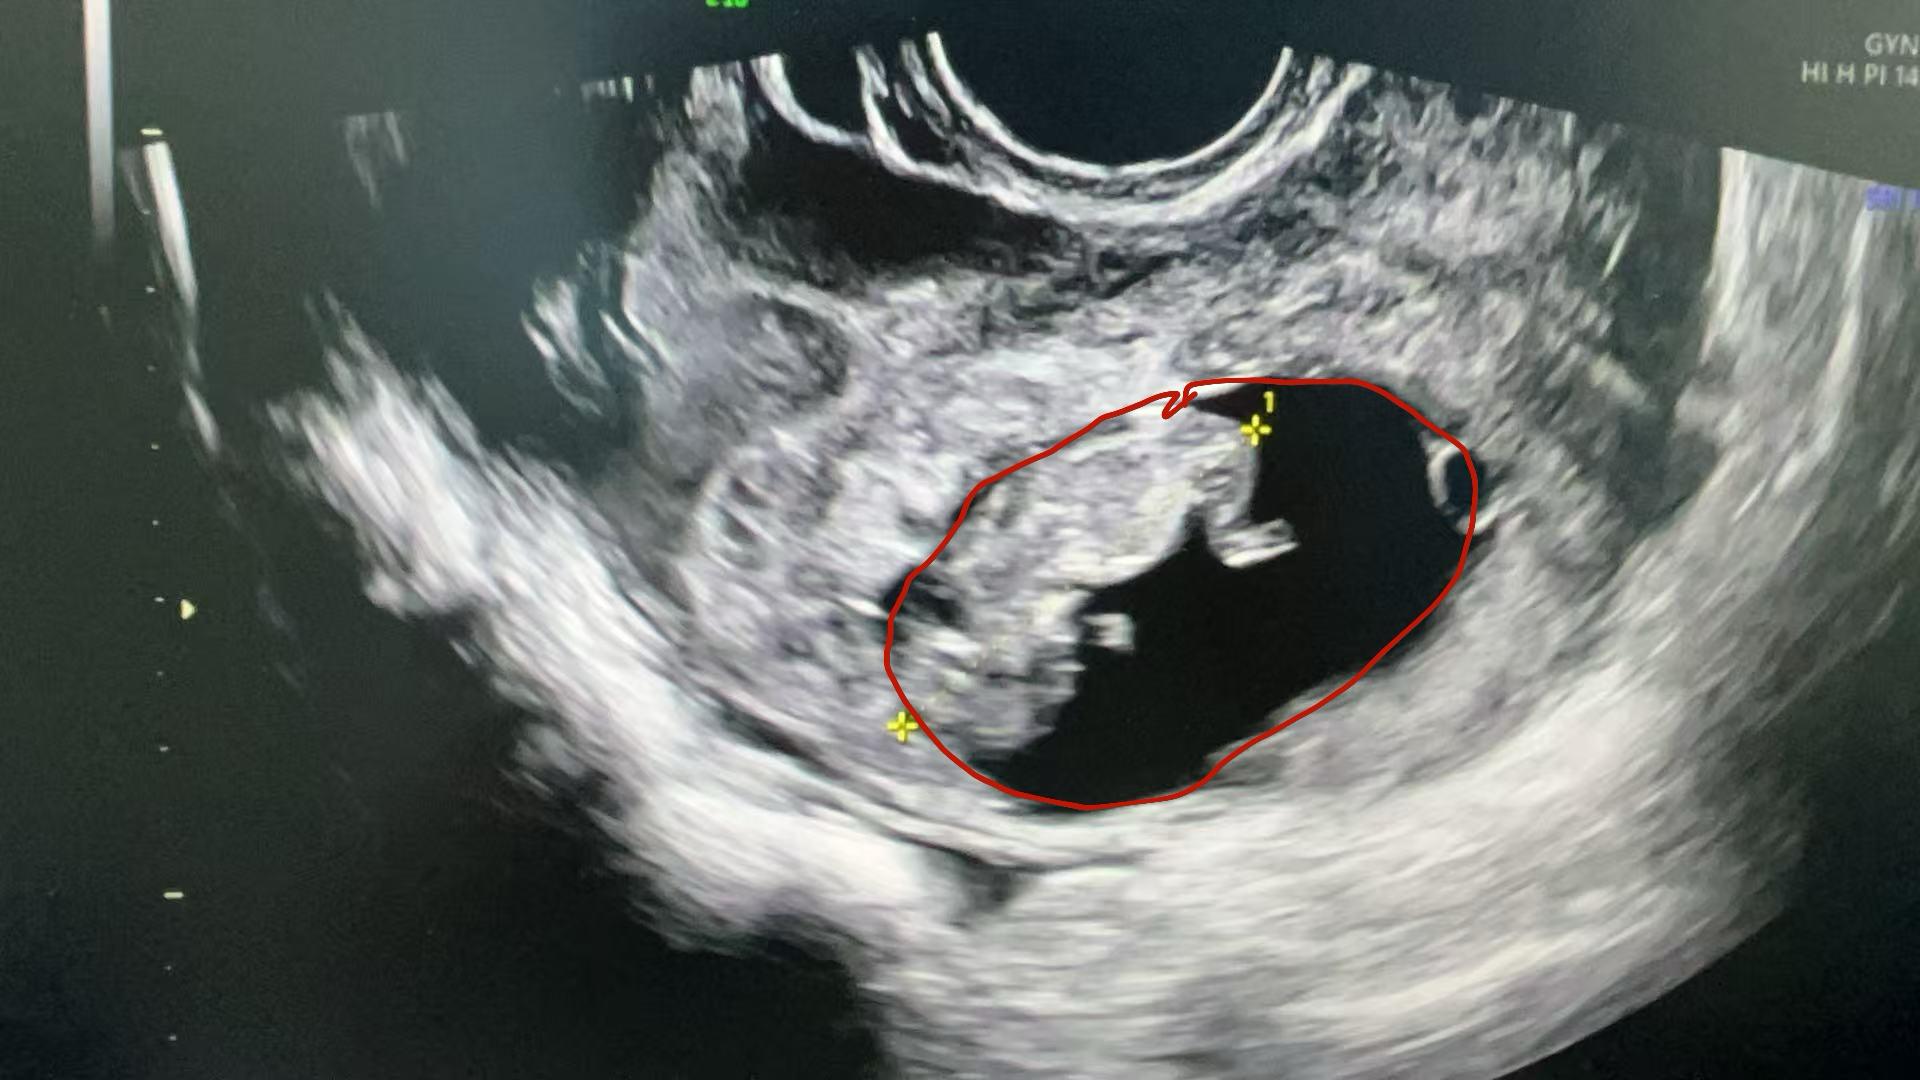

“患者入院时血压偏低,面色苍白,腹痛剧烈,还伴有阴道流血。”据妇产科一区主任黄佼介绍,经询问病史,得知患者近两个月来有不规则阴道流血,以为自己来了月经,没想到会突发剧烈腹痛。通过紧急完善妊娠检查和超声检查,发现患者尿妊娠试验呈阳性,超声显示盆腹腔大量积血,子宫左上方有一混合回声包块,里面有胚胎及原始心搏,考虑为罕见的“腹腔妊娠”,需要立即进行手术。

黄佼立即启动绿色通道,通知妇产科、麻醉手术科、输血科多学科团队迅速集结。患者在送入手术室的时候意识几近丧失,“打开腹腔时,血液像喷泉一样涌出,出血量达2200ml——相当于人体总血量的40%!妊娠组织位于子宫外左上方,大网膜内可见有‘胎心’的孕囊。”黄佼描述,经多学科团队紧张有序的抢救,迅速止血并清除妊娠组织,成功挽救了患者的生命。

腹腔妊娠分为原发性和继发性两类。原发性腹腔妊娠极为少见,是指受精卵直接种植于腹膜、肠系膜、大网膜等处。而继发性腹腔妊娠则往往发生在输卵管妊娠流产或破裂之后,胚胎落入腹腔,部分绒毛组织仍附着在原着床部位,并继续向外生长,附着于盆腔腹膜及邻近脏器表面。小谷就属于继发性腹腔妊娠,术中,医生发现患者左侧输卵管壶腹部有破裂及活动性出血,而从破口掉出去的妊娠囊被腹腔大网膜包裹,得以继续存活。